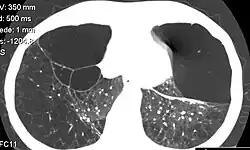

Die bedeutendste Manifestation bei Homozygoten ist die chronisch-obstruktive Lungenerkrankung (COPD). Diese tritt meist erst nach dem 30. Lebensjahr auf. Das Lungenemphysem und die Komplikationen der COPD können über die respiratorische Insuffizienz zur Hypoxämie mit möglicher Rechtsherzinsuffizienz und Cor pulmonale zum Multiorganversagen führen. In einigen Fällen kann sich auch die Atempumpe erschöpfen und eine Hyperkapnie mit einem erhöhten arteriellen Kohlendioxidpartialdruck als Komplikation hinzukommen.

- Emphysem, betrifft vorwiegend die Unterlappen und verursacht Bullae